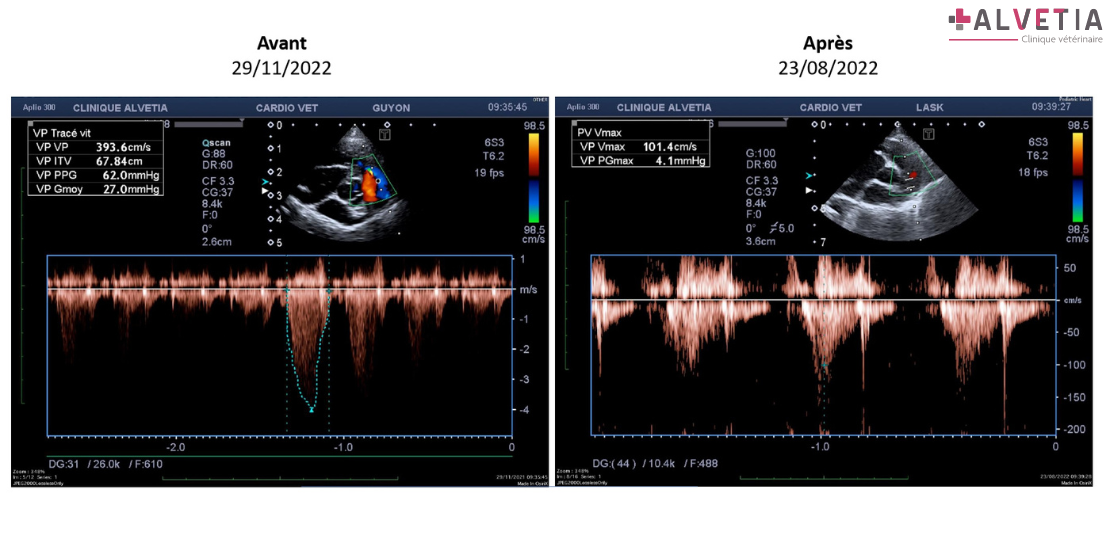

• La dysplasie tricuspidienne sévère était compliquée d’une sténose pulmonaire (vitesse au niveau de la valve pulmonaire 3,93m/s (𝘀𝗹𝗶𝗱𝗲 𝟯 𝗮𝘃𝗮𝗻𝘁), soit un gradient de pression de 62mmHg). Le ventricule et l’oreillette droite était très dilatés et des thrombi étaient formés dans cette dernière. Rodolphe a pu sortir d’hospitalisation trois jours plus tard. Après sevrage en oxygène, il a été placé sous clopidogrel 18,75 mg SID, IECA 0,5mg/kg SID, β-bloquant 6,25mg SID.

En mai et août 2022, deux nouvelles échocardiographies ont été réalisées et une stabilisation des images échographiques a été obtenue. La vitesse de régurgitation tricuspidienne est fixée à 2m/s (𝘀𝗹𝗶𝗱𝗲 𝟮 𝗮𝗽𝗿𝗲̀𝘀) (2,75m/s en novembre 2021), la vitesse au niveau de la valve pulmonaire à 1m/s (𝘀𝗹𝗶𝗱𝗲 𝟯 𝗮𝗽𝗿𝗲̀𝘀) (3,93m/s en novembre 2021). Le ventricule et l’oreillette droite restent dilatés mais sans volute préthrombique.